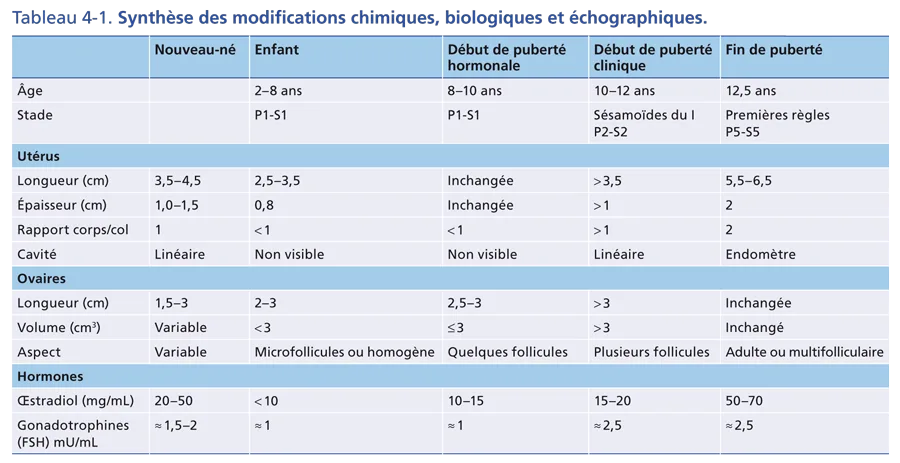

L’apparition des caractères sexuels secondaires survient entre 8,5 et 13 ans chez 95 % des filles et débute par une poussée mammaire. Pour mémoire, chez 95 % des garçons, le début de la puberté dont témoigne le développement testiculaire se situe entre 10 et 13,5 ans. L’accroissement progressif de la pilosité pubienne, le développement mammaire, testiculaire et pénien sont cotés selon les 5 stades de Tanner (fig. 4-10). La durée moyenne entre la poussée mammaire initiale et les menstruations est d’environ 2 ans. Chez le garçon, le développement pubertaire est en moyenne complet en 3 ans. Parallèlement, se produit une accélération de la vitesse de croissance staturale avec une maturation osseuse progressive cotée sur la radiographie de la main selon l’atlas de Greulich et Pyle.

Sur le plan biologique, l’activation de l’axe gonadotrope est marquée par une sécrétion pulsatile de GnRH (Gonadotropin Releasing Hormone) hypothalamique qui provoque une sécrétion également pulsatile de gonadotrophines hypophysaires. L’élévation du taux plasmatique des stéroïdes sexuels, œstradiol et testostérone, est concomitante. L’ensemble des modifications chimiques, biologiques et échographiques est résumé dans le tableau 4-1.